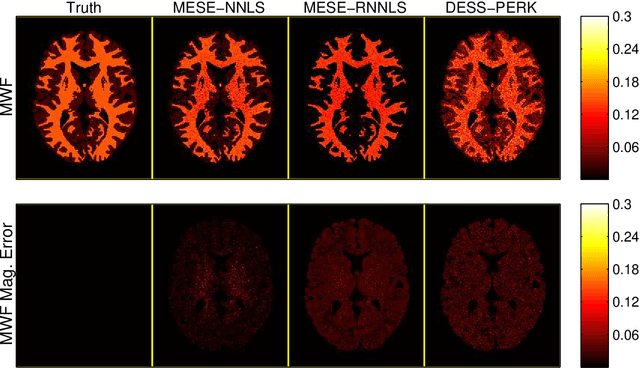

Abstract:Purpose: To investigate the feasibility of myelin water content quantification using fast dual-echo steady-state (DESS) scans and machine learning with kernels. Methods: We optimized combinations of steady-state (SS) scans for precisely estimating the fast-relaxing signal fraction ff of a two-compartment signal model, subject to a scan time constraint. We estimated ff from the optimized DESS acquisition using a recently developed method for rapid parameter estimation via regression with kernels (PERK). We compared DESS PERK ff estimates to conventional myelin water fraction (MWF) estimates from a longer multi-echo spin-echo (MESE) acquisition in simulation, in vivo, and ex vivo studies. Results: Simulations demonstrate that DESS PERK ff estimators and MESE MWF estimators achieve comparable error levels. In vivo and ex vivo experiments demonstrate that MESE MWF and DESS PERK ff estimates are quantitatively comparable measures of WM myelin water content. To our knowledge, these experiments are the first to demonstrate myelin water images from a SS acquisition that are quantitatively similar to conventional MESE MWF images. Conclusion: Combinations of fast DESS scans can be designed to enable precise ff estimation. PERK is well-suited for ff estimation. DESS PERK ff and MESE MWF estimates are quantitatively similar measures of WM myelin water content.